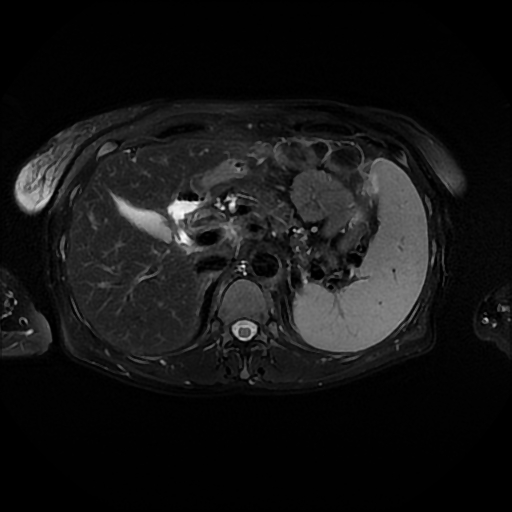

Nefes tutabilen ve tutamayan hastalara yönelik sekanslar kullanılır. Yüksek rezolüsyonlu ve dinamik karaciğer görüntülemesi(LAVA),MR pankreatiko kolanjiografi tetkiklerinde bilier ve pankreatik kanallar noninvazif görüntülenebilmekte, hızla tanısal amaçlı ERCP incelemelerinin yerini almaktadır.MR ürografi tetkikleri yapılır.